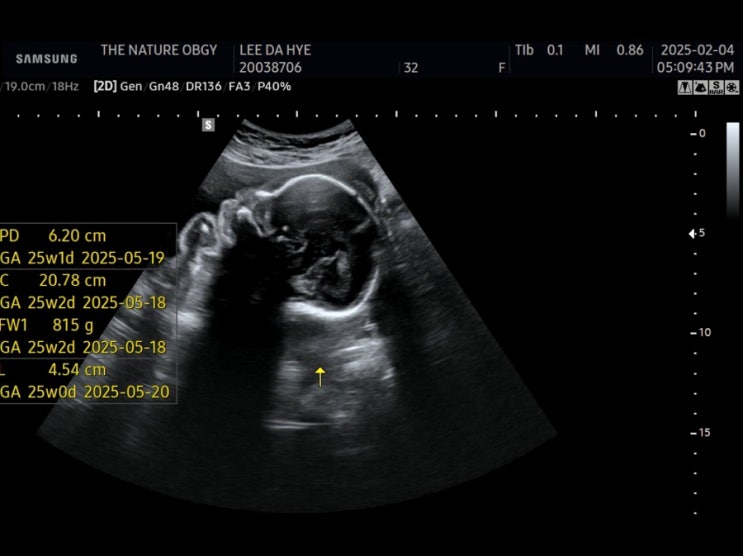

임신 23주 ~ 25주 - 점심식단 , 손목마사지기 , 하이체어 구입 , 기저귀가방 , 공포의 임당검사

임신 23주 이유식 시기 메모 거의 매일 점심은 그래놀라 ㅎ 임산부는 팔목 잘 지켜야하니까 지금부터 꾸준...